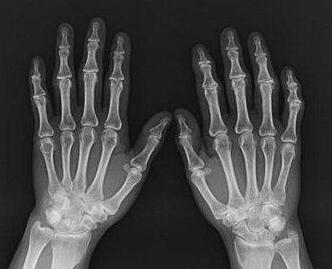

(图:类风湿性关节炎复发,万先生手部明显严重红肿)

【检查情况】

经过我院杜爱华主任的询问和检查,结果显示:ASO(—)RF(+) ESR:99mm/h,确诊为类风湿性关节炎。针对于万先生的病情,杜爱华主任决定为其制定了治疗计划。